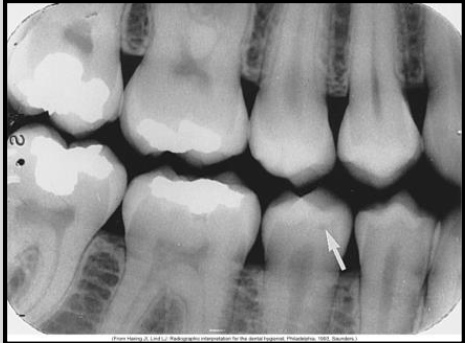

What class of interproximal caries is this?

Class 4 Severe